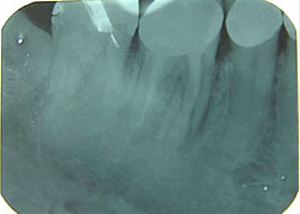

-8-上下・18本の土台のついたレントゲン所見

右下

第一第臼歯近心根破折

(大臼歯は歯根が二つに分かれている)

1.H18.4.12

抜歯後

(某歯科医院にて手前の歯根のみ抜歯)

2.インプラントする前

(抜歯後4ヶ月弱)